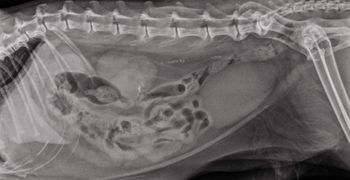

The use of computed tomography (CT), though not readily available at every institution, is becoming a more widespread modality for use in the small animal patient. Computed tomography affords a rapid evaluation of skeletal images with a small slice thickness that can be as small as 0.625.